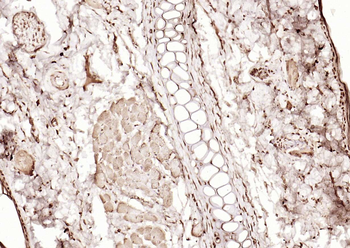

100 μl, 50 μl, 200 μl - ATF4 Recombinant Rabbit Monoclonal Antibody [orb704304]Featured

FC, ICC, IF, IHC-Fr, IHC-P, WB

Human

Mouse

Rabbit

Recombinant

Unconjugated

50 μl, 100 μl - MARK3 Recombinant Rabbit Monoclonal Antibody [orb704310]Featured